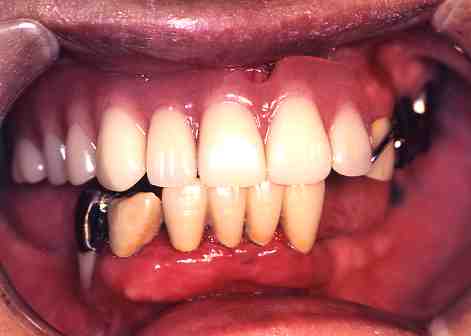

【歯科用レーザーによる治療】

(2)歯周病の治療

1.術前

下の歯のまわりの

歯ぐきが腫れています。